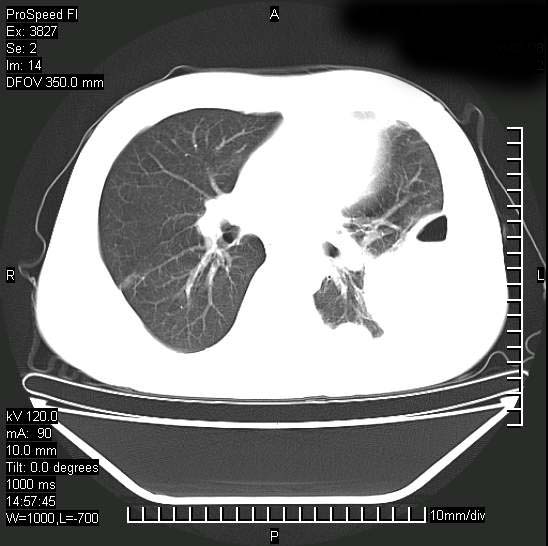

男性,一月前出现右侧肋区疼痛,较剧烈,干咳,无发热,自诉使用抗炎药后缓解,几天前又出现左侧剧烈疼痛,

发热,体温38。9,今天ct,考虑左侧包裹性脓胸,胸腔积液,右上中肺小斑片影,结核/炎症?胸水未见恶性细胞。

支持:脓胸!并双肺继发性肺结核!

脓胸!并双肺继发性肺结核!

左侧肺脓疡,化脓性胸膜炎(脓胸),不支持结核诊断,建议继续抗感染治疗

支持左侧肺脓肿并脓胸,肺内炎症,建议继续抗炎治疗后复查。

脓胸没问题,肺内还可见感染灶,感觉不像是结核性病变.